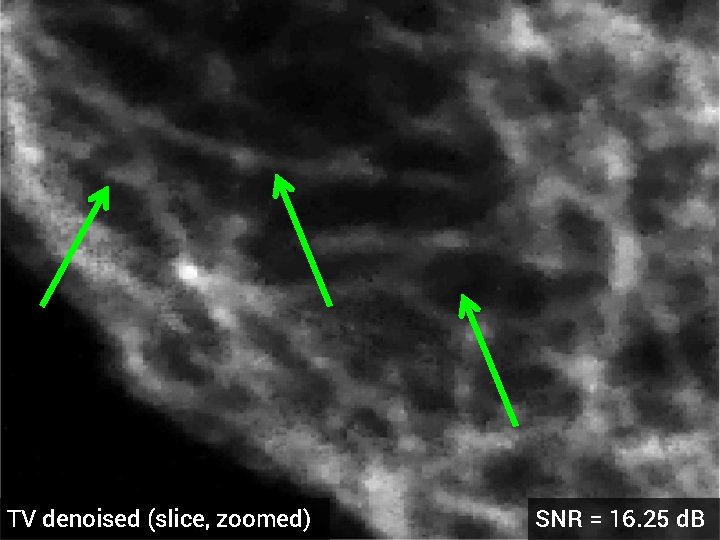

TV denoised (slice, zoomed) SNR = 16. 25 d. B

Deblurring of 3 -D Florescence Microscopy § 1024 x 17 voxels § 3 x 3 x 3 Gaussian blur kernel, std. dev = 0. 05 § 5 d. B additive Gaussian noise § Optimized regularization parameter original dataset (z-slice)

Blurred + Noisy (slice, zoomed)

TV deblurred (slice, zoomed) SNR = 14. 50 d. B

HDTV 3 deblurred (slice, zoomed) SNR = 15. 23 d. B